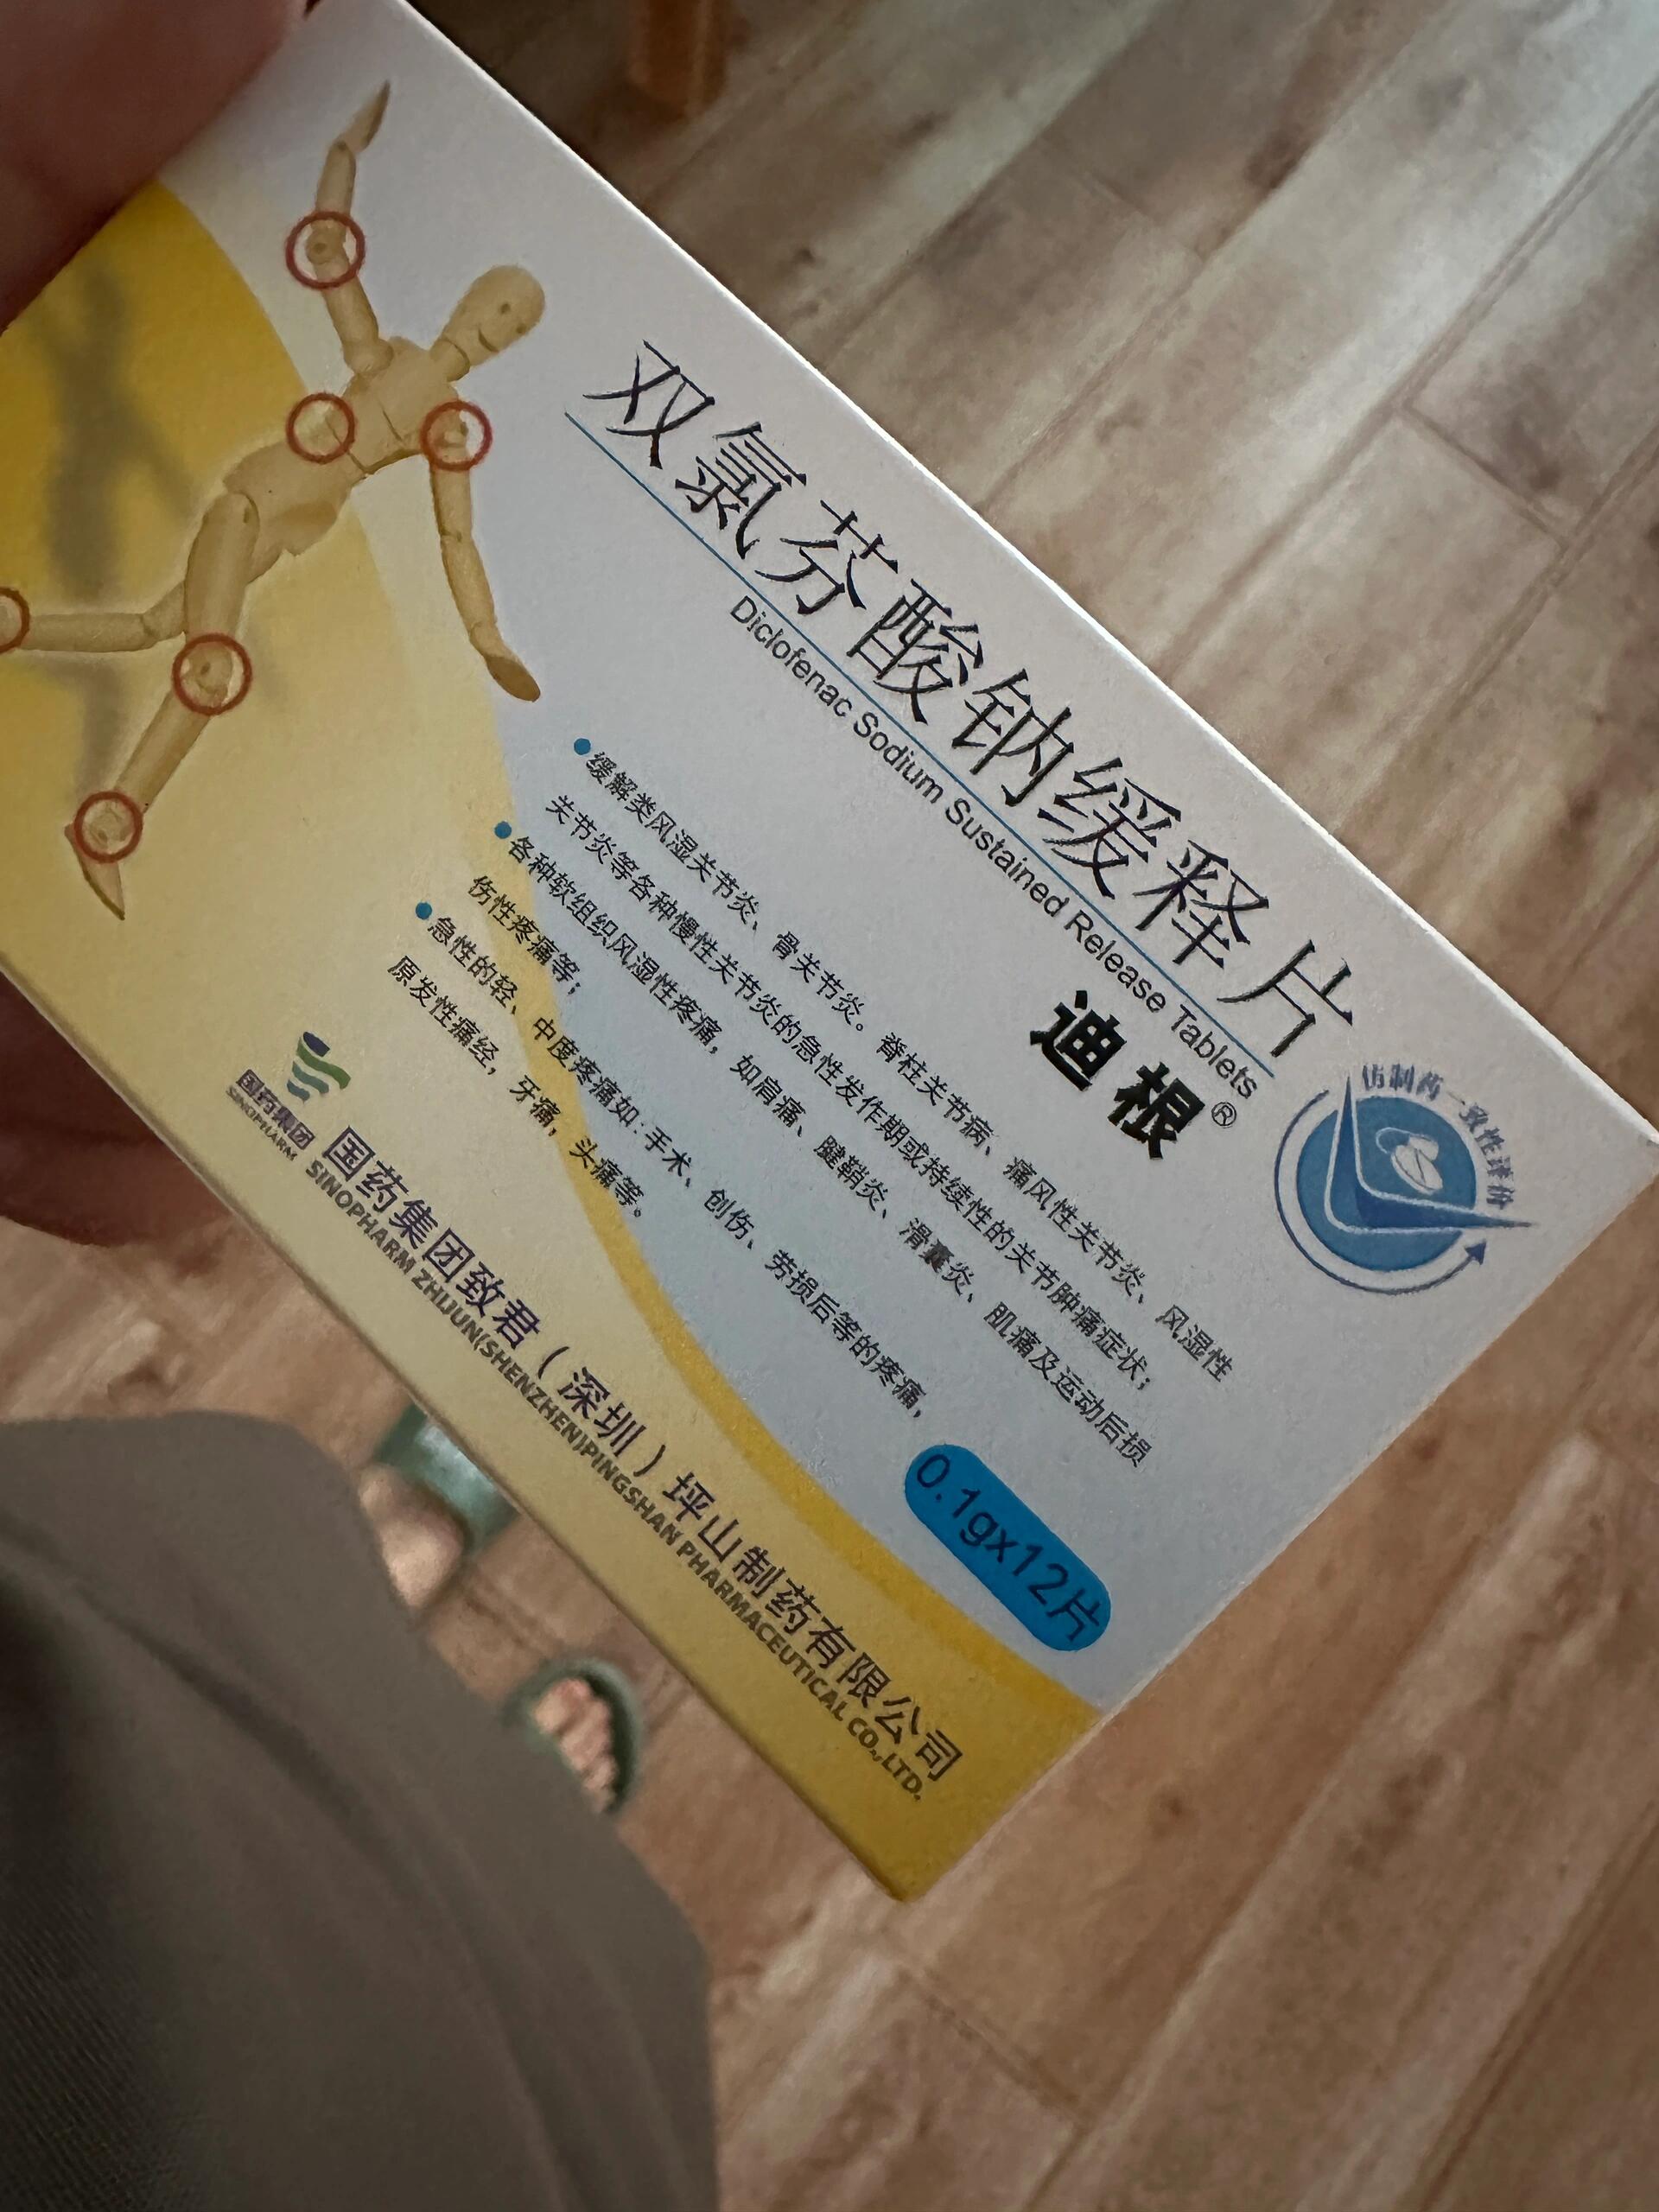

迪根双氯芬酸钠缓释片12片类风湿痛风关节肿痛腰腿疼痛腱鞘炎滑囊炎

迪根止痛药类风湿骨关节炎脊柱关节病痛风性风湿性关节炎关节肿痛

双氯芬酸钠缓释片迪根手指骨关节炎专用膏药贴风湿性痛风止痛膏

迪根止痛药类风湿骨关节炎脊柱关节病痛风性风湿性关节炎关节肿痛

1g*12片/盒肌肉疼痛滑囊炎类风湿关节炎痛风急慢性关节炎骨关节炎

双氯芬酸钠缓释片迪根专治类风湿性关节炎祛风湿治疗骨关节炎的药

迪根止疼药类风湿骨关节炎脊柱关节病痛风性风湿性关节炎关节肿痛

迪根止疼药类风湿骨关节炎脊柱关节病痛风性风湿性关节炎关节肿痛